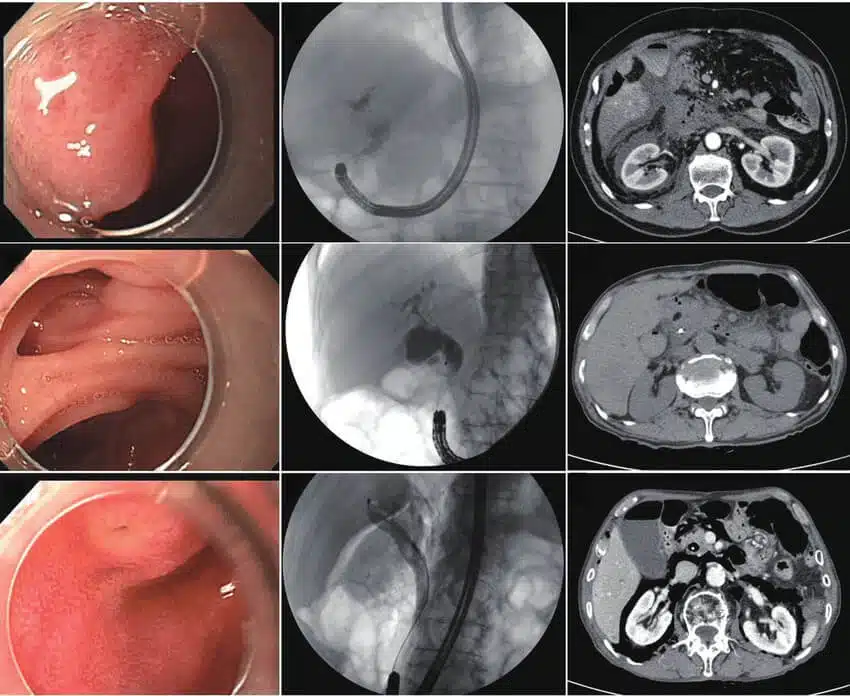

ماذا يحدث أثناء تصوير البنكرياس والأقنية الصفراوية بالتنظير الباطني بالطريق الراجع ERCP ؟

يتم إجراء تصوير البنكرياس والأقنية الصفراوية بالتنظير الباطني بالطريق الراجع ERCP في العيادة أو المستشفى. يمكن استخدام هذا التصوير لحالات تشخيصية أو علاجية بناءً على حالتك. تعامل مع الإجراء بسهولة لأنك لن تشعر بأي ألم أثناء تصوير البنكرياس والقنوات الصفراوية بالمنظار. إذا كان لديك أي استفسار حول المخاطر المتعلقة بإجراء تصوير البنكرياس والقنوات الصفراوية بالمنظار ، أخبر الجراح ليقوم بتقديم المزيد من المعلومات حول العملية ونتائجها. إن نجاح عملية ERCP (تصوير البنكرياس والقنوات الصفراوية بالتنظير الداخلي) عالية وينتج عنها دائماً الكثير من المزايا وهذا هو السبب في استخدامه على نظاق واسع.